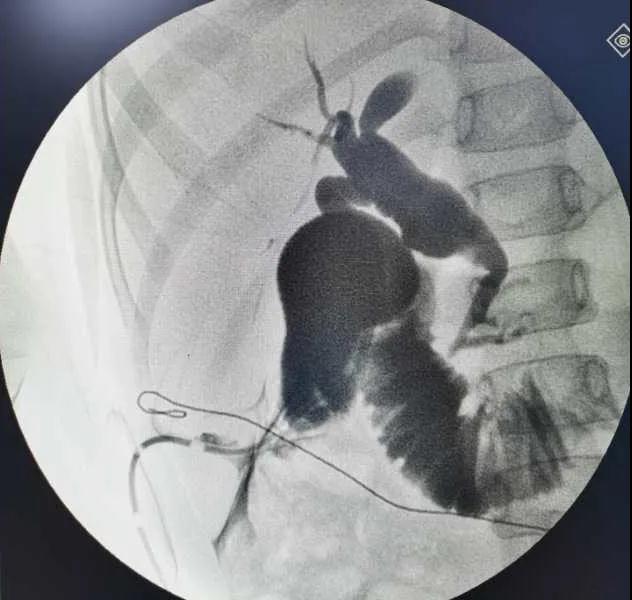

5月7日,西安國際醫(yī)學(xué)中心醫(yī)院小兒外科郭正團(tuán)教授團(tuán)隊成功為1名膽總管囊腫患兒進(jìn)行了腹腔鏡膽管造影 腹腔鏡膽總管囊腫切除 腹腔鏡肝管空腸吻合術(shù)。目前,患兒恢復(fù)良好,已正常進(jìn)食。

入院后,謝崇醫(yī)生積極為患兒完善術(shù)前準(zhǔn)備,MRCP(核磁共振膽道水成像)顯示該患兒為膽總管囊腫Ic型,有明顯的胰膽合流異常。面對復(fù)雜的病情,小兒外科郭正團(tuán)主任立即組織團(tuán)隊進(jìn)行術(shù)前討論,制定了完善的手術(shù)方案及應(yīng)急措施。

5月7日,一切準(zhǔn)備就緒,郭正團(tuán)主任主刀,帶領(lǐng)小兒外科團(tuán)隊進(jìn)行腹腔鏡膽管造影 腹腔鏡膽總管囊腫切除 腹腔鏡肝管空腸吻合術(shù)。術(shù)中,患兒膽總管與周圍肝動脈及門靜脈粘連嚴(yán)重,給手術(shù)增加了難度。郭正團(tuán)主任沉著冷靜,操作嫻熟,完整剝離了膽總管囊腫及遠(yuǎn)端胰腺段膽管,肝總管與空腸完成了Roux-en-Y吻合,手術(shù)進(jìn)行順利。術(shù)后第2天,玲玲就可以下床活動;第6天,已正常飲食。